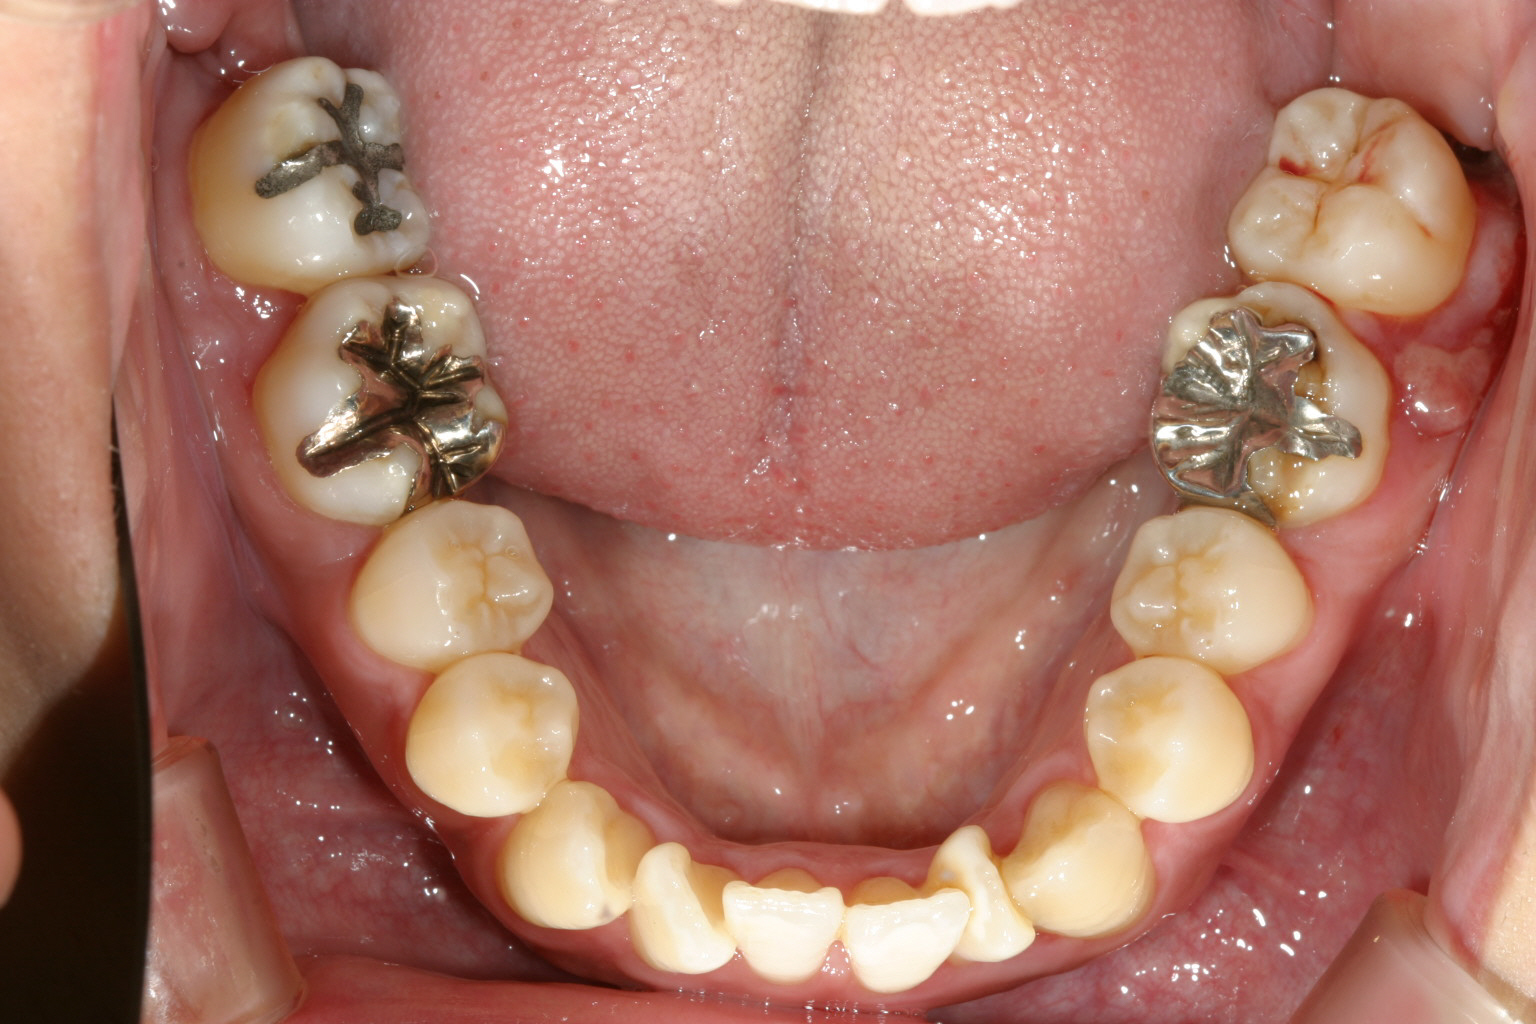

下顎の両側切歯が90度回転しています。 これが難儀なんです。 ワイヤーを留める為のブラケットを何度か貼りなおす必要が有ります。

上と下の歯が閉じず開咬状態です。

下顎はこの90度回転した歯に悪戦苦闘しています。笑